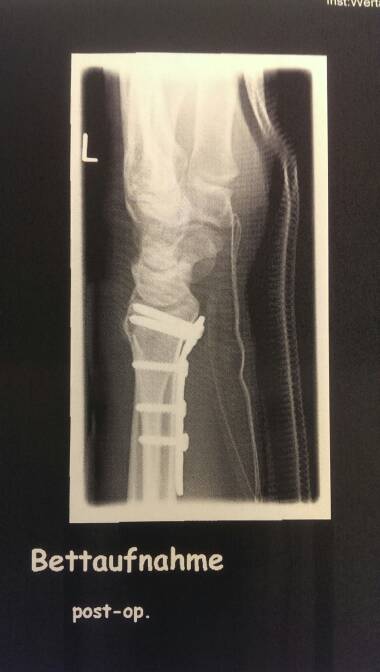

Aber dies ist wohl nicht mein bike jahr. Erst hat mich ein sturz im April für fast 10 wochen außer gefecht gesetzt und jetzt kommt noch ein operierter schleimbeute hinzu. Was auch nochmal 4-6 wochen genesung veranschlagt, damit ist mein Alp-X auch ins wasser gefallen